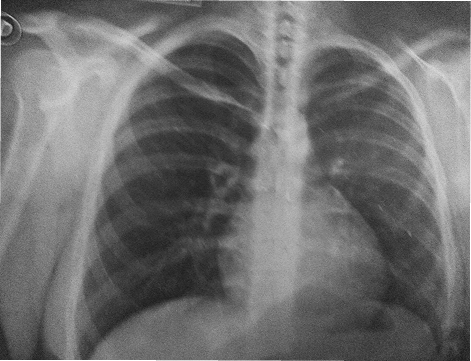

Paciente Esthefany Medina

Paciente diagnosticada con hipertrofia cardíaca (cardiomegalia), una condición caracterizada por el agrandamiento del corazón debido al engrosamiento de sus paredes musculares o la dilatación de sus cavidades.

Evolución del corazón inflamado

2011